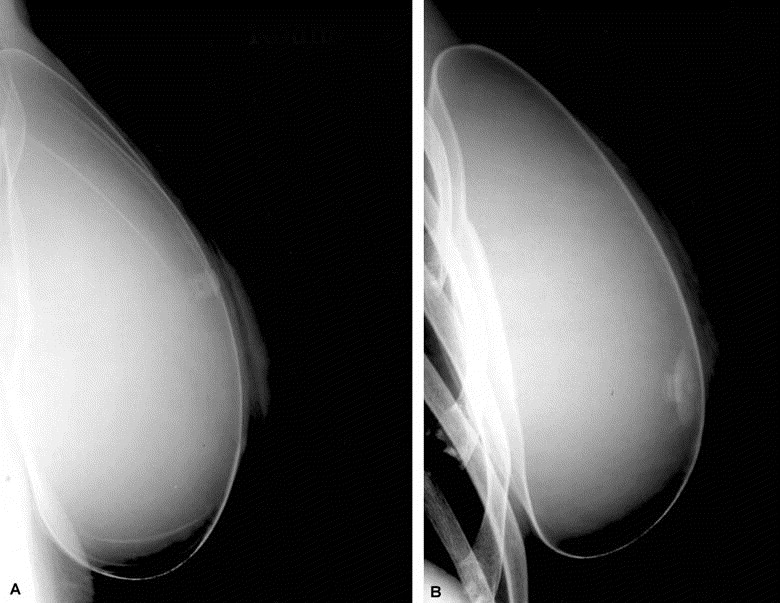

Tear Drop Implants (Anatomical Implants)

Tear drop implants, also known as anatomical or contoured implants, are shaped like a natural breast, with a sloped contour that fills out more at the bottom than the top, mimicking the natural shape of a breast. They are often chosen by individuals who seek a more natural appearance.Advantages of tear drop implants include:Our expert surgeons help you to choose the most suitable breast implant type for you considering your body type, natural breast tissue, and aesthetic goals.